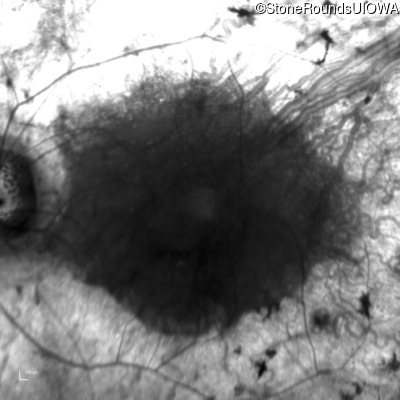

Infrared Fundus Photograph - Right - 20/25 -1

Exemplar